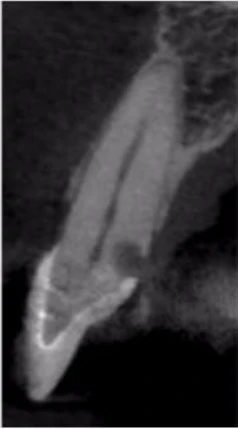

Tuy nhiên sau khi chụp 3D, tôi đã có thể thấy mức độ tiêu xương ở lát cắt ngang, đứng dọc, đứng ngang; điều may mắn là nó không vượt ra khỏi phạm vi răng (hình 18 và 19).

Hình 18: Lát cắt ngang răng 31 trên CBCT

Hình 19: Lát cắt ngang răng 41 trên CBC

Tôi quyết định theo dõi răng 46 và tiến hành điều trị răng 31, 41 bằng Ca(OH)2 (hình 20). 3 tuần sau hẹn bà tới trám bít ống tủy (hình 21). Bà quay lại để tái khám sau 1 năm vào mùa hè 2017. Kết quả điều trị coi như đã thành công, không thấy tiêu xương thêm (Hình 22). Hơn thế, răng 46 không thay đổi tình trạng tiêu. Có phim CBCT giúp theo dõi sự thay đổi về kích thước và mức độ tiêu xương trên răng bệnh nhân qua thời gian. Ngoài ra, CBCT cũng cho biết khi nào không nên điều trị, tôi đã tự tin chỉ cần theo dõi răng 46 từ đó hạn chế điều trị không cần thiết cho chính mẹ mình.